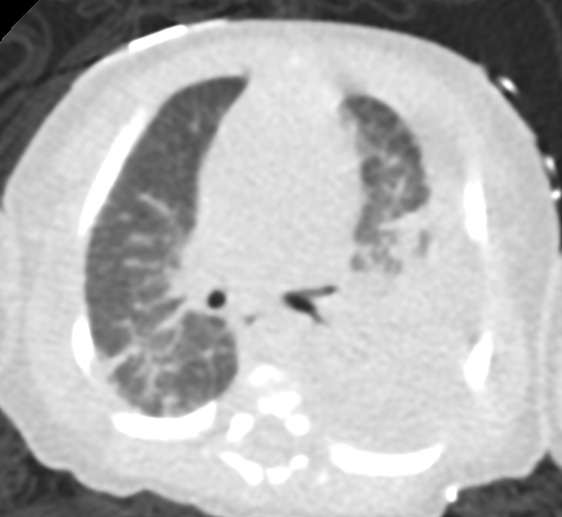

Chest x-ray: Demonstrated left-sided consolidation and pleural effusion( Fig-1) Subsequent chest CT revealed diffuse interstitial and septal thickening (Fig 2). She was admitted for management of worsening respiratory status, requiring chest tube placement and HFNC.

Our patient’s chest CT shows diffuse or segmental interlobular septal thickening, perihilar infiltrates, ground-glass opacities, and hyperinflation. These findings, when combined with pleural effusions, increase the likelihood of Congenital Pulmonary Lymphangiectasia (CPL). CPL is a rare congenital disorder of pulmonary lymphatic development. It is characterized by dilated lymphatic channels draining the interstitial and subpleural spaces of the lung. The incidence of CPL among stillborn and neonates is estimated to be <1%. The etiology of CPL is unknown, but it is suspected to have a genetic background.

Chest radiographic findings include prominent interstitial markings, hyperinflation, ground-glass opacities especially in neonates, and pleural effusion. Chest CT may show diffuse or segmental interlobular septal thickening, perihilar infiltrates, ground-glass opacities, and hyperinflation (Fig 3). Pleural fluid analysis is consistent with chylous pleural effusion. Diagnostic criteria include a milky or opalescent appearance of the pleural fluid, elevated triglyceride levels(typically >110mg/dl), and lymphocyte predominance on cell count. In neonates and young infants who may not yet be enterally fed, triglyceride levels may be lower, therefore diagnosis may rely on lymphocyte predominance(>80%) and increase in triglyceride content following initiation of enteral feeds. These findings support impaired lymphatic drainage, as seen in congenital pulmonary lymphangiectasis. Lung biopsy with histology and immunochemical staining demonstrating dilated lymphatic channels and thickening of the interlobular septa and subpleural space is the gold standard for diagnosis. Immunohistochemical staining for endothelial cell markers CD31, CD34, and D2-40 confirms lymphatic origin. Echocardiogram should be performed to rule out pulmonary venous obstruction, such as hypoplastic left heart syndrome or TAPVR, which can cause secondary lymphangiectasia. Lymphangiograms have been used in some patients to evaluate thoracic duct disruption and lymphatic duct dilation. In our patient Echocardiogram showed large left pleural effusion, PFO with bidirectional flow, mild bilateral pulmonary artery stenoses, and normal biventricular systolic function.